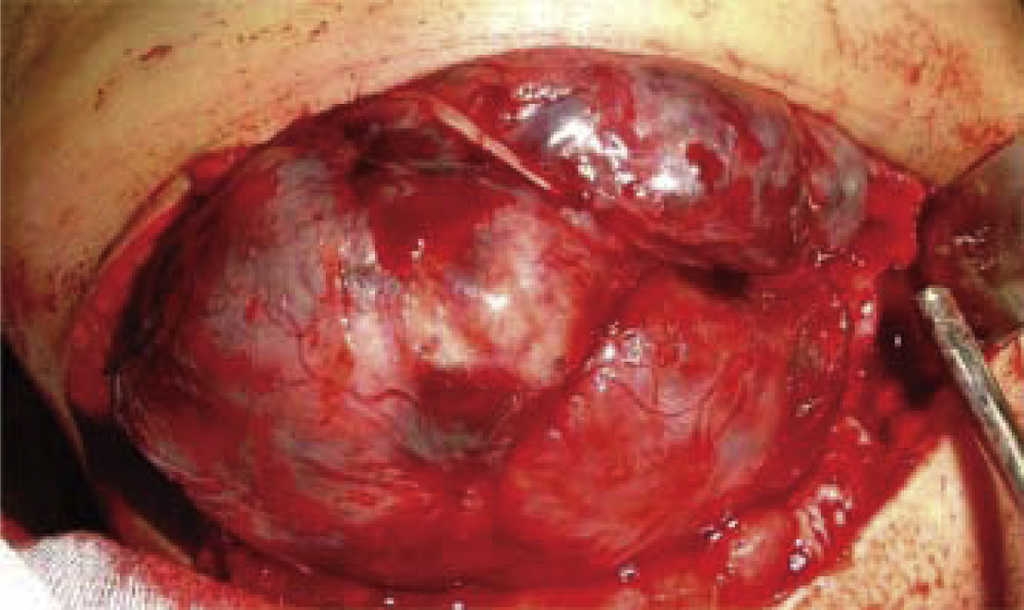

La tomografía tridimensional confirma extensa destrucción ósea (Figura 2). No hay ataque al estado general de salud, ni signos o síntomas generales. Laboratorios dentro de parámetros normales. El resultado de biopsia incisional reporta osteoblastoma benigno mandibular. Dada la amplia destrucción, y el comportamiento local agresivo de la lesión se realiza hemimandibulectomía derecha (Figura 3).

Paciente femenina de ocho años de edad acude a la consulta con aumento de volumen hemimandibular izquierdo, de cinco meses de evolución, crecimiento rápido, doloroso (Figura 6). Intraoralmente se observa expansión de cortical vestibular con desplazamiento de órganos dentales (Figura 7). Radiográficamente se distingue una lesión que destruye parte de cuerpo y rama mandibular izquierda, pero conservando cóndilo y apófisis coronoides (Figura 8). No presentan datos generales de importancia y los exámenes de laboratorio se presentan con parámetros normales. El resultado de biopsia incisional fue ameloblastoma plexiforme mandibular. Tomando en cuenta la conducta clínica agresiva local de la lesión, se realiza excisión en bloque (Figura 9). Se coloca prótesis de reconstrucción conservando cóndilo y apófisis coronoides (Figura 10). En el postoperatorio no se observan complicaciones y se conservan estructuras nerviosas y motoras; buena apertura bucal, y adecuado aspecto facial (Figura 11).